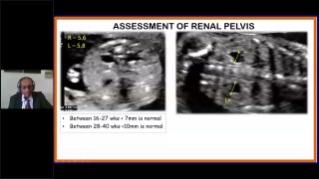

Con la tecnologĂa de la avanzada plataforma ZST+, las soluciones inteligentes completas de la serie Nuewa estĂĄn dise?adas especialmente para mejorar la salud de las mujeres durante el perĂodo previo al embarazo, el embarazo y la recuperaciĂłn en el posparto, con el fin de brindar diagnĂłsticos integrales y eficientes para enfrentar desafĂos clĂnicos cada vez mĂĄs exigentes.